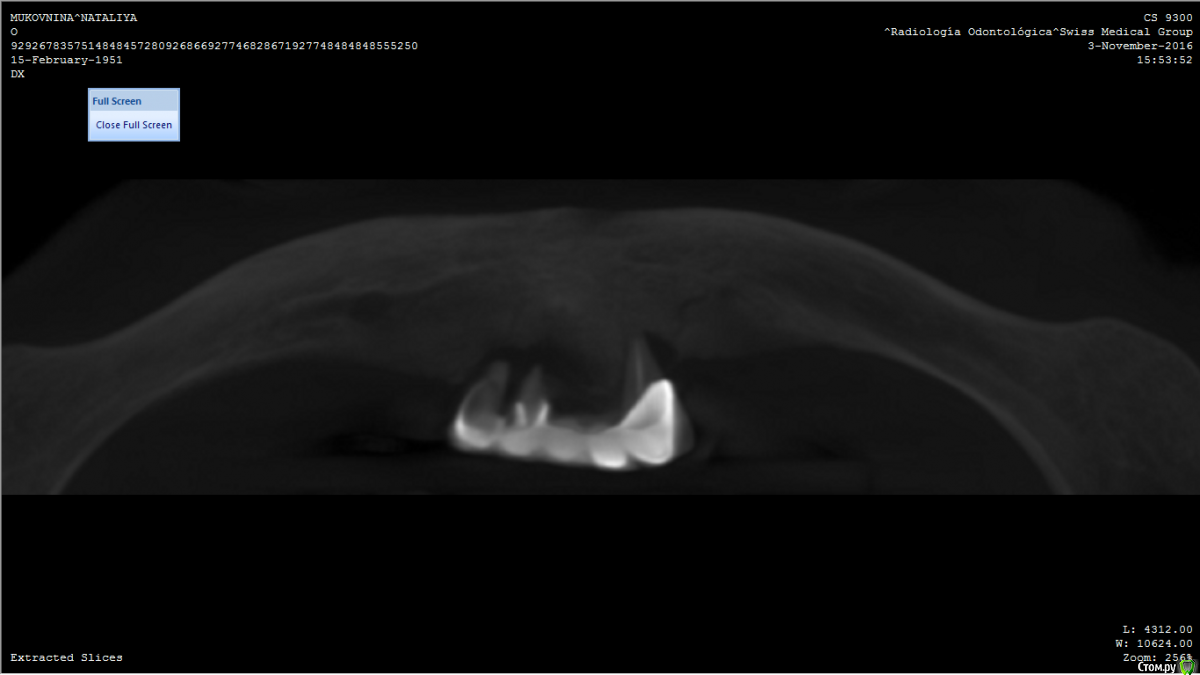

Oxi78 Опубликовано 18 декабря, 2016 Поделиться Опубликовано 18 декабря, 2016 ЗдравствуйтеЖенщина 65 лет. Полная адентия и атрофия. Подскажите пожалуйста можно ли протезировать на имплантах? ( All in 4) Кости судя по сканам не достаточно.Можно ли сделать наращивание кости? Не получается открыть все файлы компьютерной томографии.Спасибо Ссылка на комментарий

Oxi78 Опубликовано 19 декабря, 2016 Автор Поделиться Опубликовано 19 декабря, 2016 Спасибо за ответ. Сопутствующие заболевания остеопороз, аутоимунный тиреоидит в не тяжелой форме. Консультировались с эндокоинологом. Он разрешил имплантацию зубов. Никаких таблеток не принимает. Один раз в год укол от остеопороза. Общее самочуствие хорошее. Ходили на прием к имплантологу( женщина проживает в Аргентине). Врач сказал что только вставные протезы. Импланты вкручивать не куда. На верхней челюсти тоже мало кости. 1.Можно ли рассчитывать на НКР(направленную костную регенерацию)? 2.Нужно ли сделать новую компьютерную томографию? Не хотелось бы ставить простые протезы. Спасибо. Ссылка на комментарий